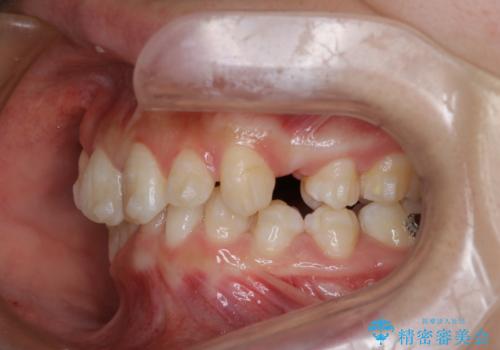

- 前歯のガタガタを主訴に来院されました。

抜歯を行い、インビザラインにて治療を完了しております。